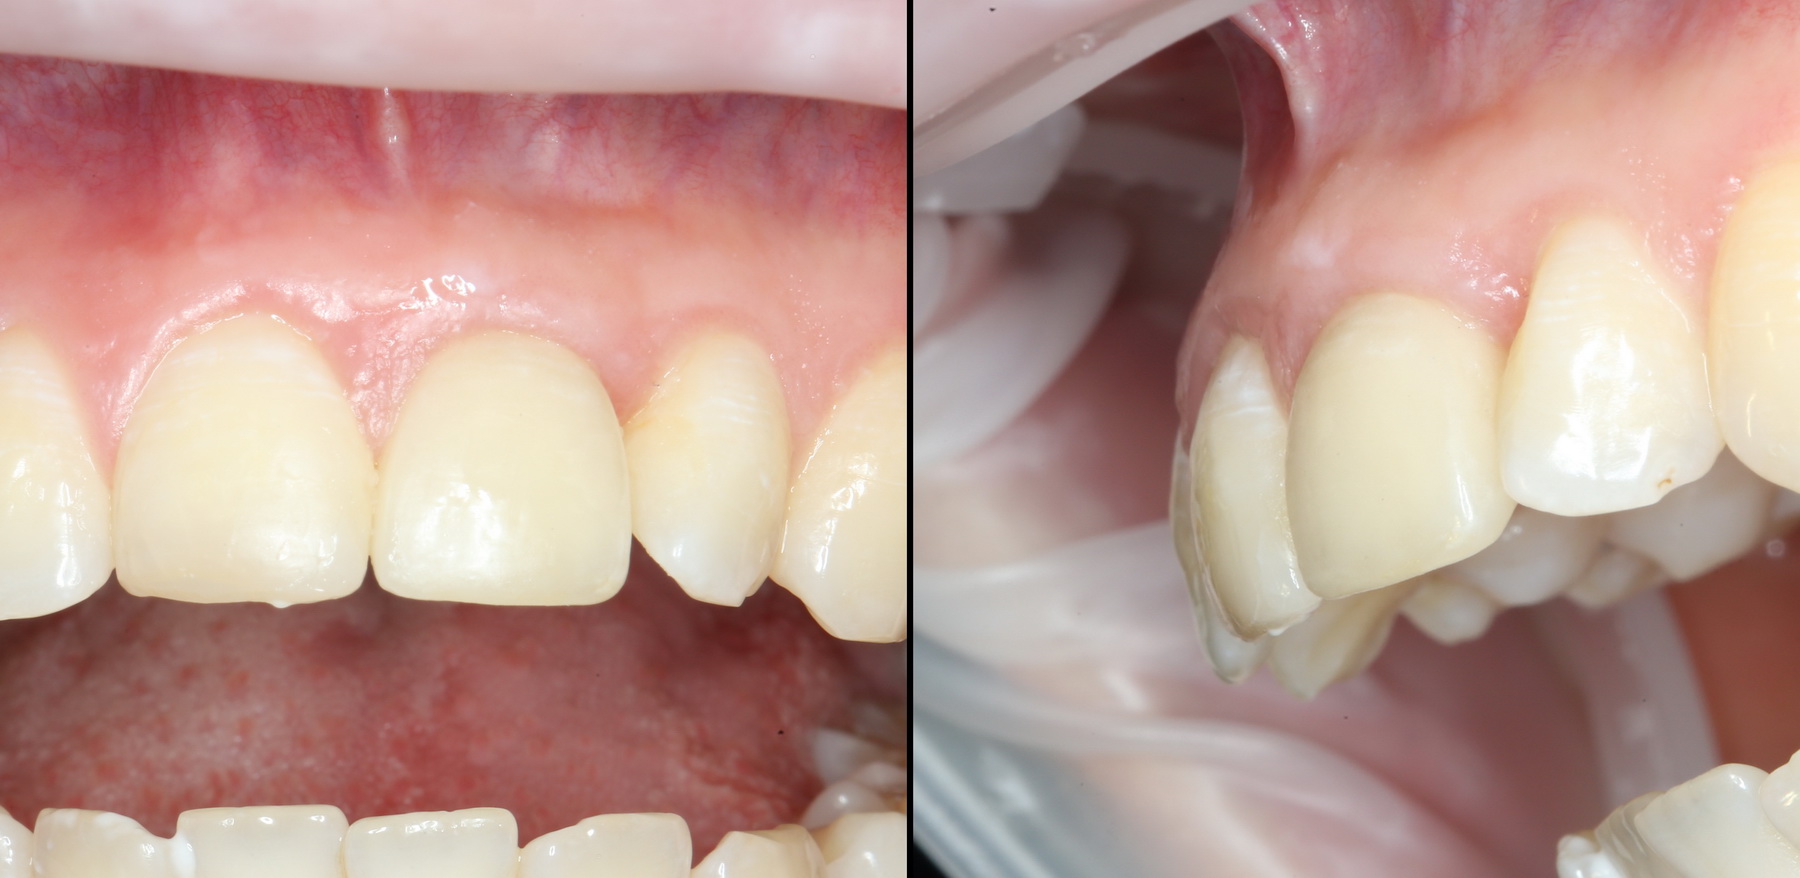

Нам остается просто поставить формирователи десны:

A09A6628 (2) A09A6629 (2)

и подождать, пока вокруг них сформируется плотная слизистая оболочка. Потом мы направляем пациента к ортопеду для протезирования.

Хирургический этап имплантологического лечения закончен.